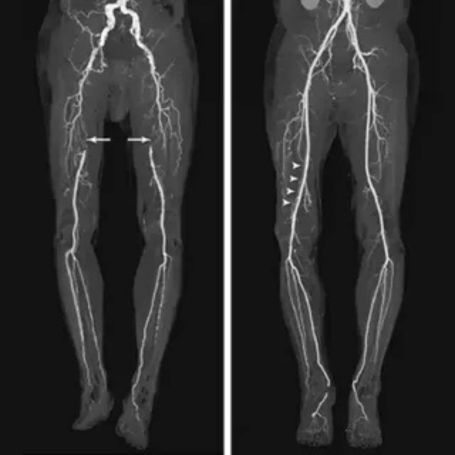

CT Lower Limb Angiography (CT Lower Limb Angio) is a non-invasive imaging test used to visualize blood vessels in the legs. It helps detect blockages, narrowing, or abnormalities in arteries and veins that supply blood to the lower limbs. This test plays a crucial role in diagnosing Peripheral Artery Disease (PAD) and other vascular conditions.

2. Assessment of peripheral artery disease: It helps doctors understand the severity and exact location of arterial narrowing or occlusions.

4. Image reconstruction: High-speed computers create detailed 3D images, which radiologists interpret to identify any vessel abnormalities.

2. Region covered: From abdominal aorta to feet arteries